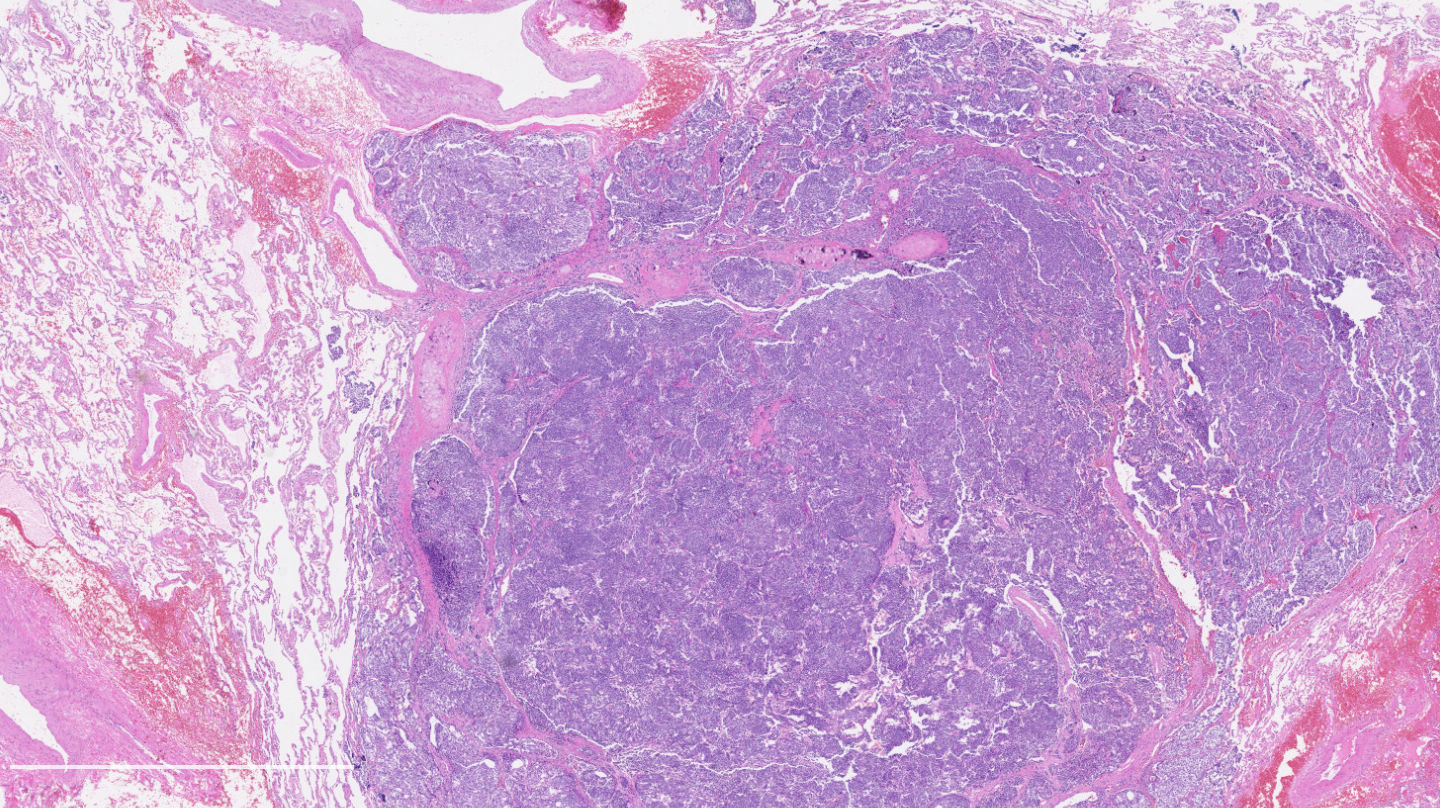

Contributed by Philippe Joubert, M.D., Ph.D.

- A patient undergoes a lobectomy for a well circumscribed nodule. On H&E slide, the tumor exhibits a well differentiated neuroendocrine morphology and you observe the histologic features presented in the image. Which of the following statements is true?

B. It is defined as a well differentiated neuroendocrine tumor with 2 - 10 mitoses per 2 mm² or foci of necrosis. The picture shows a carcinoid lung tumor with a classical neuroendocrine morphology and 2 mitoses in 1 high power field. Even though the whole tumor is not presented here, the presence of 2 mitoses is sufficient for an atypical carcinoid diagnosis.